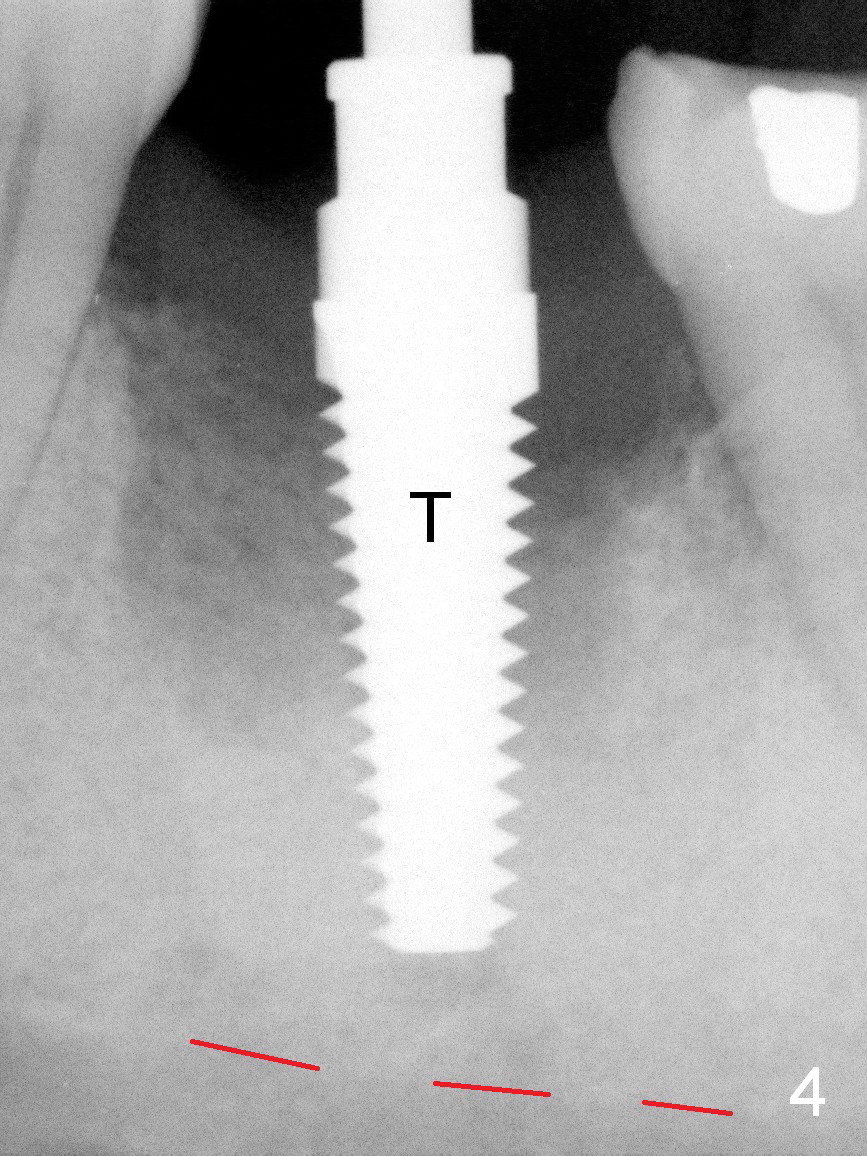

A 37-year-old lady (MP) presents to clinic with chief complaint of bad smell from lower right crown (Fig.1: #19; red dashed line: superior border of the Inferior Alveolar Canal). One of the most prominent pathologies is fracture of the distal root (<). After extraction, the socket is treated with 2% Xylocaine/1:50,000 Epinephrine. The coronal distobuccal plate is defective. Osteotomy is initiated as lingual as possible. The 1st intraop PA shows that the osteotomy is shallow and distal to the almost non-existent septum (Fig.2 S). The osteotomy is intended to move more mesially, but the result is not obvious when 4.5x14 mm drill is in place (Fig.3 D). The depth of the osteotomy is increased by 3 mm; a 5x17 mm tap is stable (Fig.4 T). A 5x12 mm implant (Fig.5 I) is placed until it cannot be turned. The implant is higher than the distal crest (^). In addition there is space apical to the implant (Fig.5*). After 5 mm drill is used, the implant is seated deeper with insertion torque < 35 Ncm (Fig.6). It suggests overprep. Anyway, an immediate provisional is fabricated after placement of an abutment (A). After reline, the provisional fits well. It has to be removed with forceps for occlusal adjustment. Finally the abutment/implant complex turns in the socket with fingers. The rotation/position of the complex is randomly adjusted. When the provisional is cemented, it does not seat completely, but is stable. If the implant osteointegrates, the provisional must play a role in stabilizing the implant. Bone graft is placed in the gap prior to cementation (Fig.6 *).